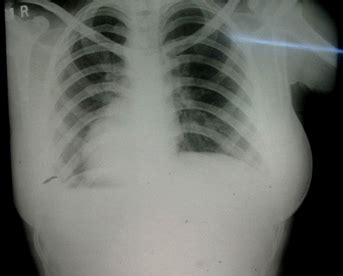

papillary cheggcdn thorax